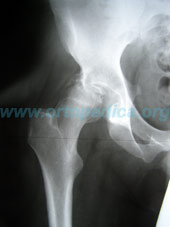

Рентенограмма до операции